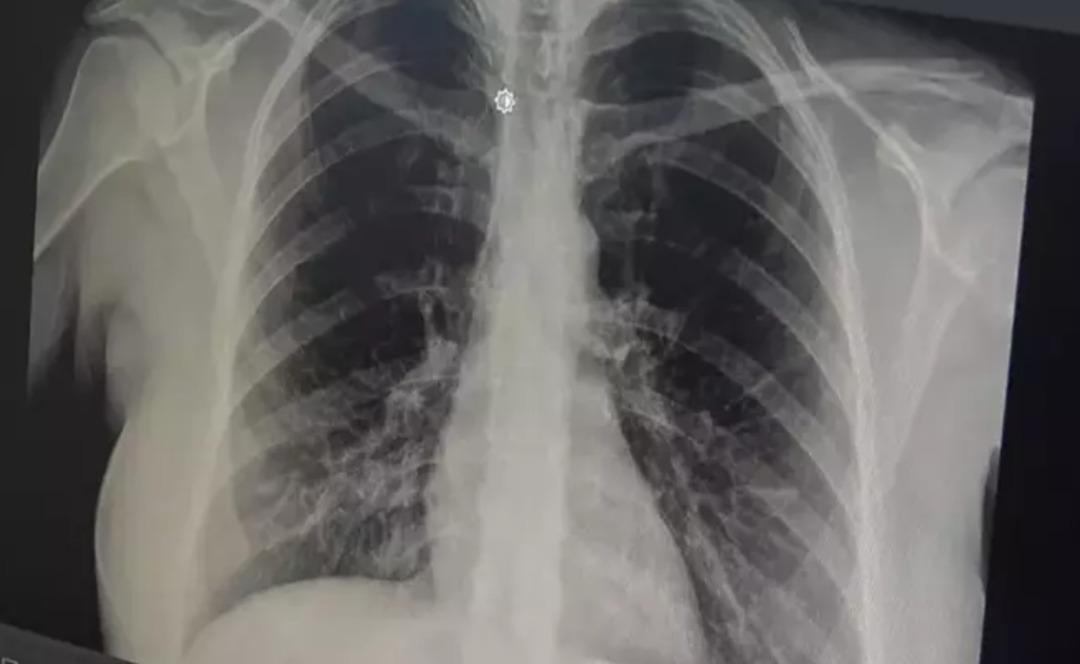

Göğüs Hastalıkları Uzmanı Prof. Dr. Tevfik Özlü, akut bronşitin giderek yayıldığına dikkat çekerek önerilerde bulundu. prof. Akut bronşitin ilk belirtilerinin boğaz ağrısı, hafif ateş ve burun akıntısı olduğunu ancak enfeksiyon bronşlara yayıldığında göğüs ağrısı ve şiddetli öksürüğün ortaya çıktığını söyleyen Dr. Özlü, akut bronşitin hafif ve tedavi edilebilir bir hastalık olduğunu belirterek, hastaların doktora başvurması konusunda uyardı.

prof. Akut bronşitin solunum yolu virüslerinin neden olduğu bir hastalık olduğunu belirten Dr. Özlü, şöyle konuştu: “Günümüzde çok sık gördüğümüz bir hastalık. Genelde hastalar şöyle tarif ediyor: 'Öncelikle boğazım ağrıyordu, boğazım ağrıyordu. hafif ateş, burun akıntısı, hapşırma, geniz akıntısı ve öksürük “2-3 gündür göğsümdeydi. Nefes alırken acı hissediyorum. Göğsünde bir çalı varmış gibi geliyor ve. Nefes aldığımda oraya sıkışıp kalıyor.” Enfeksiyonun göğse kadar indiğini iddia ediyorlar. Bu doğrudur çünkü akut bronşit, solunum yolu virüslerinin neden olduğu bulaşıcı bir hastalıktır. Bu enfeksiyon üst solunum yollarıyla sınırlı olmayıp aynı zamanda alt solunum yollarımız ve bronşlarımız.

Akut bronşitin en önemli belirtisinin öksürük olduğunu vurgulayan Prof. Dr. Tevfik Özlü, “Kuru öksürük veya balgamlı öksürük şeklinde kendini gösterebiliyor. Bazen belirti daha çok hırıltılı solunum ve nefes darlığı şeklinde hissedilebiliyor. Yüksek ateş genellikle herhangi bir rahatsızlığa neden olmaz ancak bazen bakteriyel enfeksiyonlar da ortaya çıkabilir” dedi.

Bronşitin genel olarak hafif bir hastalık olduğunu ancak belirtilerin artması durumunda doktora başvurulması gerektiğini belirten Özlü, şöyle konuştu: “Altta yatan kronik bir hastalık, astım veya obstrüktif KOAH gibi bir akciğer hastalığı varsa, kronik hastalığın akut alevlenmesidir. Buna eşlik edebilir ve genel akut bronşit, nefes darlığı, hırıltılı solunum, yorgunluk, yüksek ateş gibi ciddi belirtilerle ortaya çıkabilirse mutlaka doktora başvurmanız gerekir. Genel olarak hafif ve tedavi edilebilir bir hastalık olduğunu söylemek isterim” dedi.